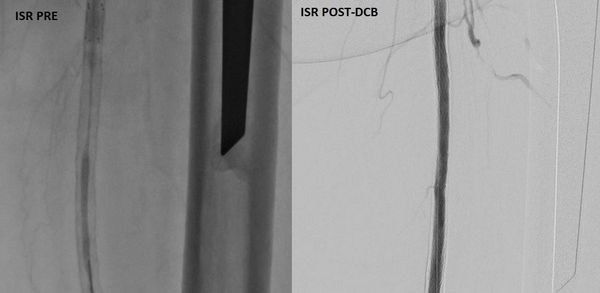

استشاري جراحة الأوعية الدموية و القسطرة التداخلية الطرفية